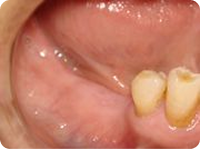

施術例④

治療前

右下の奥歯3本が欠損しています。

治療中

インプラントの土台を3本植立しました。

手術直後の写真です。